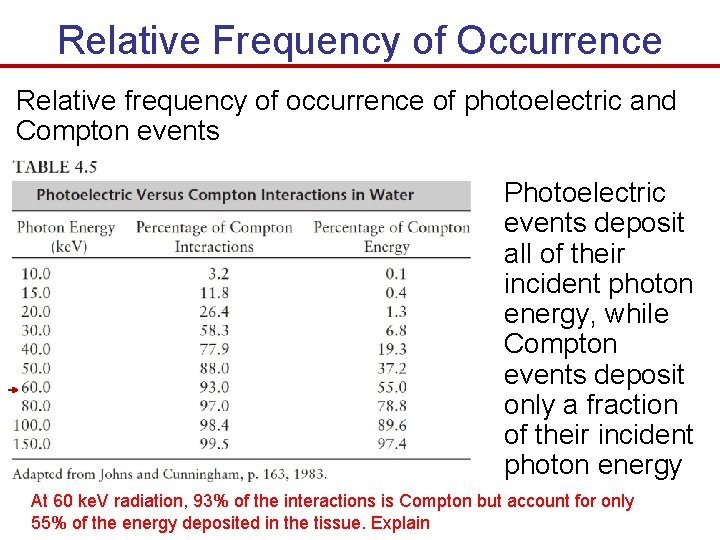

Relative Frequency of Occurrence Relative frequency of occurrence of photoelectric and Compton events Photoelectric events deposit all of their incident photon energy, while Compton events deposit only a fraction of their incident photon energy At 60 ke. V radiation, 93% of the interactions is Compton but account for only 55% of the energy deposited in the tissue. Explain